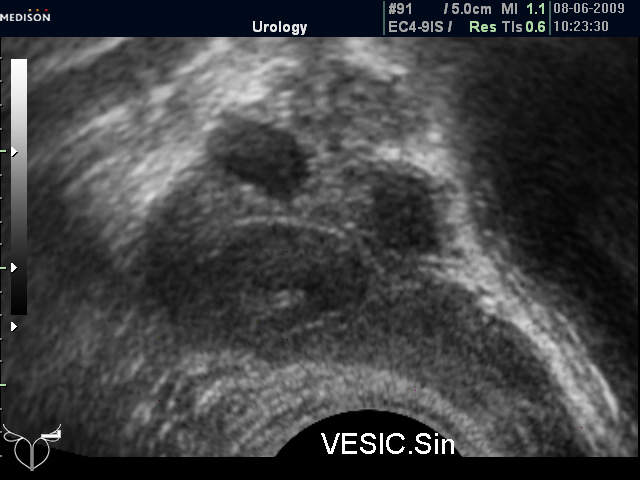

И еще "вдогонку", из вчерашнего. Правый СП 19,7 мм, левый - 23,3 мм.

ТРУЗИ левого СП